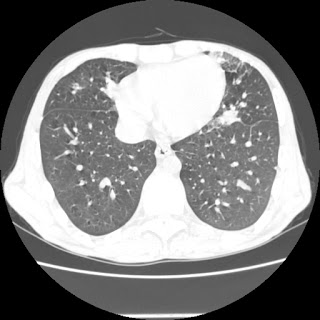

Repeat radiological images: